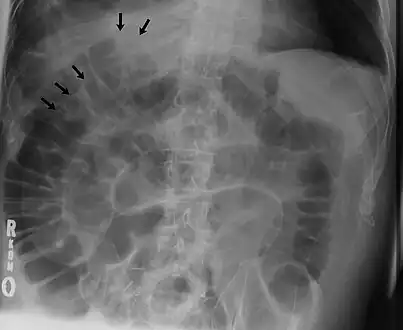

The double wall sign marks the presence of air on both sides of the intestine.[27] However, a false double wall sign can result from two loops of bowel being in contact with one another.[28] The sign is named after Leo George Rigler.[29] It is not the same as Rigler's triad.

Double wall sign. This is a secondary sign of pneumoperitoneum. Patient is supine, and air within the abdomen and lumen of the bowel accentuate both sides of the bowel wall.- Ultrasound finding of pneumoperitoneum known as "peritoneal stripe sign"[32]